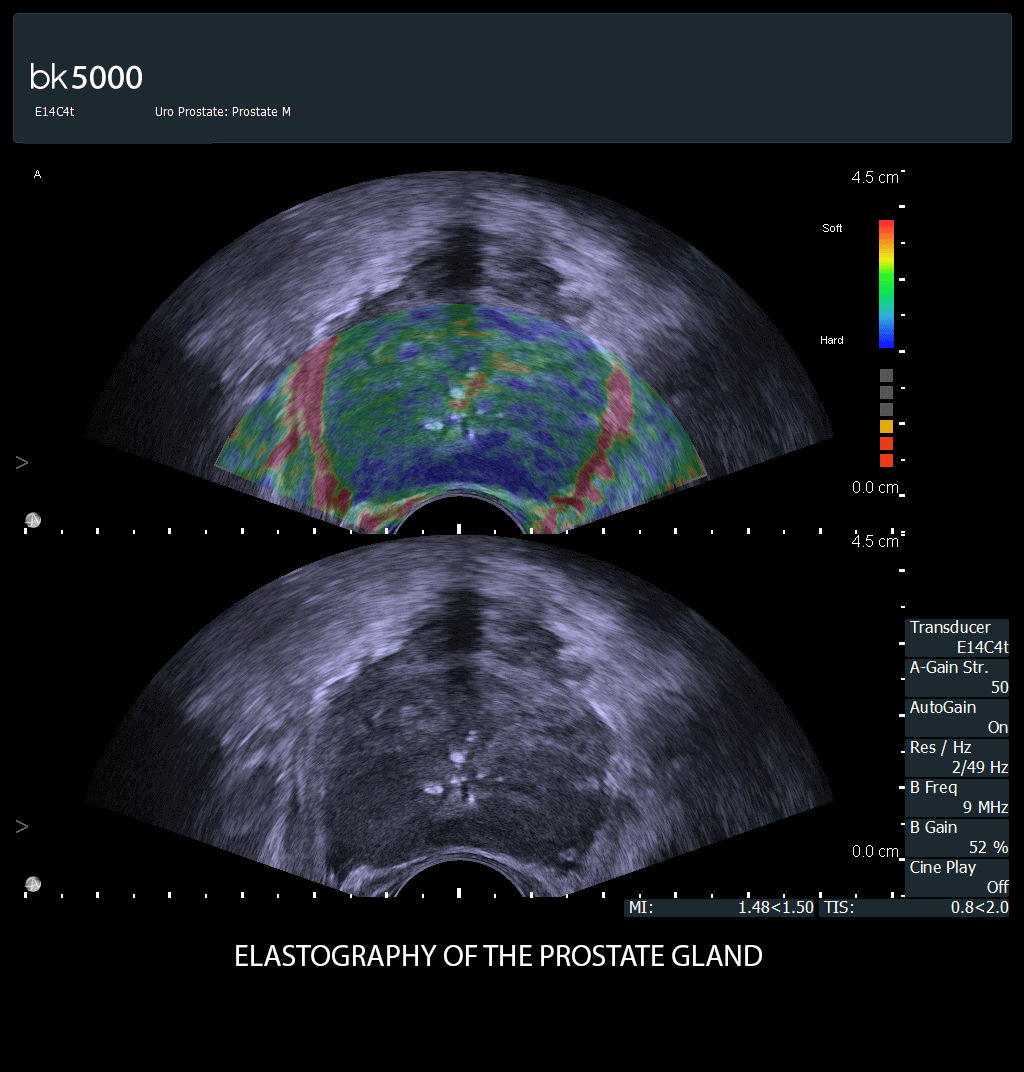

Prostate cancer treatment

Enhance your brachytherapy procedures with our advanced ultrasound guidance. Easily follow the needle path and visualize both LDR and HDR procedures. View transverse and sagittal planes on a single monitor and seamlessly integrate with planning software for precise and efficient treatment.

Ultrasound guidance for prostate brachytherapy

Brachytherapy is an effective, low-cost treatment for prostate cancer with low morbidity and high patient tolerability. Biplane transrectal ultrasound scanning is essential for accurate seed placement in the prostate gland, imaging in both transverse and sagittal planes. We lead in ultrasound-guided brachytherapy, offering precise seed placement with the Endocavity Biplane transducer. We provide both low-dose (LDR) and high-dose rate (HDR) options, integrating seamlessly with planning software like VariSeed for accurate treatment. LDR involves permanent seed implants, while HDR uses temporary implants for higher radiation doses. VariSeed software aids in planning and executing these procedures with features like easier contouring, volume measurements, and automatic calibration.